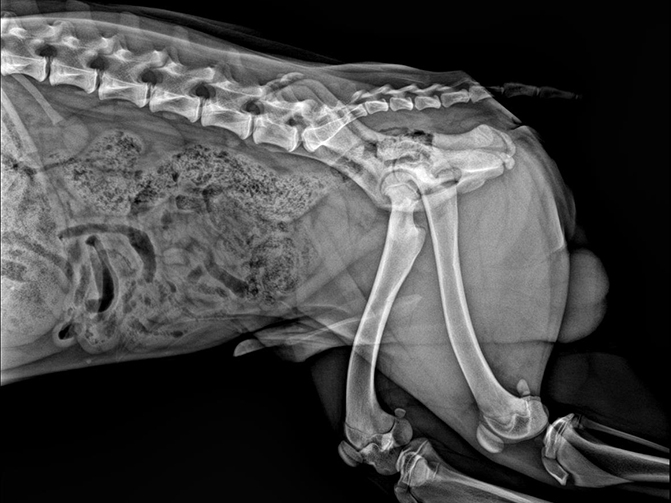

02

VET-528